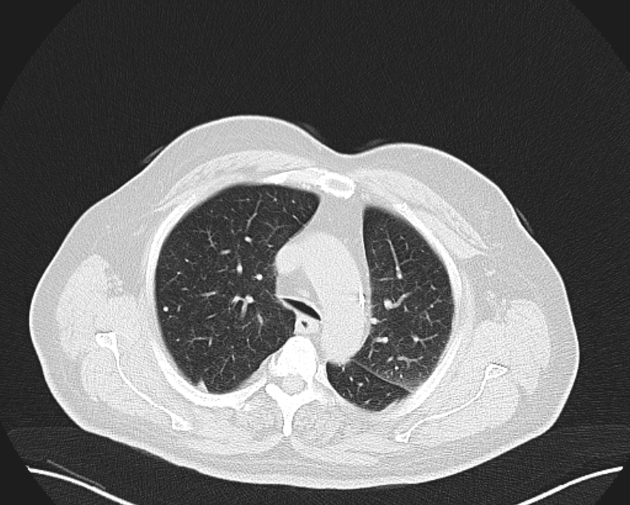

What pulmonary disease is this patient likely to develop?

Kartegners Syndrome

Triad of this condition